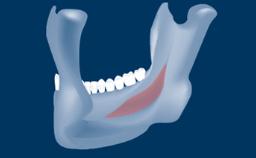

In this short microlearning module on digitally guided sinus floor elevation, we delve into a specialized aspect of the digital workflow for implant-guided surgery, focusing on the use of digital guides in the sinus floor elevation technique.

• describe the indications for digital guides in SFE

• define the manufacturing process of digital guides for SFE